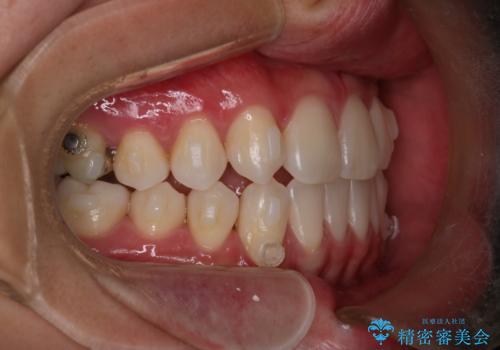

【インビザライン】歯の本数少ないのにがたつきがある セラミックインレー

- 右上2番が欠損しており、歯並びをバランスよくしたいということで来院されました。

ワイヤー装置とマウスピースで悩まれていましたが、マウスピースで治療可能と判断致しましたのでマウスピースにて治療しました。

IPR、歯列弓拡大、ゴム掛けを行い歯並びを整える治療計画を立てました。

右上2番が欠損しているため、見た目と噛み合わせの両方のバランスを整えるために経過を追いながら必要な部位にゴム掛けをしました。

また矯正後、患者様の希望で

メタルインレーをセラミックインレーにやりかえさせていただき、さらに綺麗に仕上がりました。